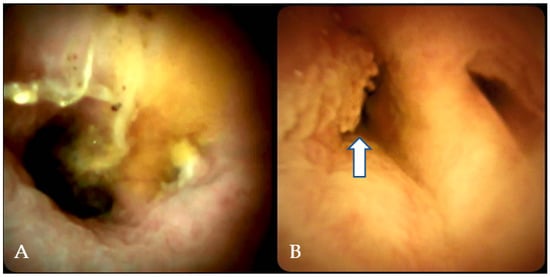

5.2. Visual Impression

5.3. Cholangioscopy-Guided Biopsy

- Kahaleh, M.; Gaidhane, M.; Shahid, H.M.; Tyberg, A.; Sarkar, A.; Ardengh, J.C.; Kedia, P.; Andalib, I.; Gress, F.; Sethi, A.; et al. Digital single-operator cholangioscopy interobserver study using a new classification: The Mendoza Classification (with video). Gastrointest. Endosc. 2022, 95, 319–326. [Google Scholar] [CrossRef]